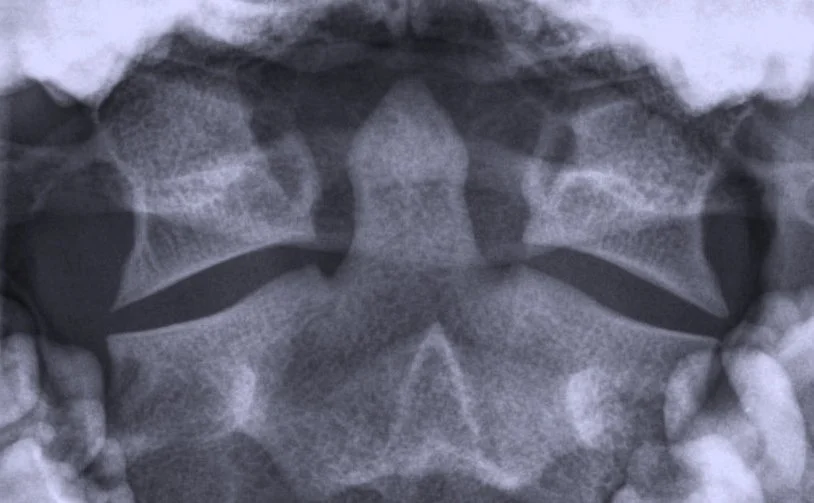

Avant toute action, il y a une analyse/appréciation. Chez nous les Chiropraticiens ça s’appelle faire une Anamnèse (on pose des questions) et un Examen (on inspecte, ausculte, teste). On arrive à un Diagnostique (on pose un nom à une certaine symptomatologie). Pour mieux discerner un problème, on va procéder à faire des radios/résonances magnétiques/scanners, une analyse de sang ou d’urine. Le Chiropraticien est autorisé à faire ces examens. En cas de doute, on envoye le patient à un autre spécialiste pour une clarification de la situation (Radiologue, Neurologue, Orthopédiste, Urologue,…). Finalement on arrive au Traitement.

-Le docteur Lindsay J. Rowe D.C., M.D., DACBR: Un géant dans la radiologie dans l’enseignement comme dans la publication des livres de radiologie. Ses cours de radiologie sont d’une finesse remarquable: le compliqué rendu simple. Un grand merci pour ses enseignements éclairer aux US au NWCC et plus tard dans des diffèrent séminaires.